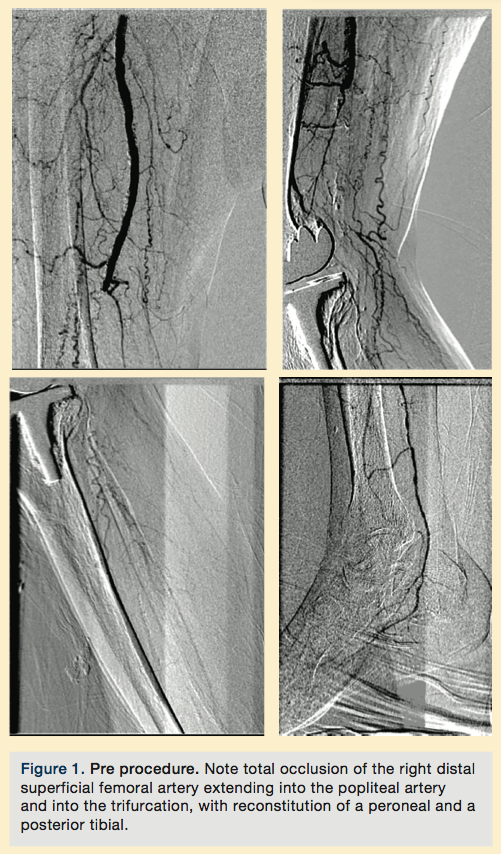

This is an 80-year-old male with history of diabetes, hypertension, hyperlipidemia, severe rest pain, and non-healing ulcers of the right lower extremity. The patient was told by 2 surgeons that he needed a below-the-knee (BTK) amputation; he was referred to us by a podiatrist.

Procedure

Peripheral angiography showed total occlusion of the right distal superficial femoral artery extending into the popliteal artery and into the trifurcation, with reconstitution of a peroneal and a posterior tibial. We attempted to obtain antegrade access to the lesions of the right infra-popliteal vessels (Figure 1). After failing to cross the lesion, we obtained retrograde access, puncturing from below the lesion through the posterior tibial artery near the ankle joint (Figure 2). Access was obtained and the lesion below the knee was crossed (Figure 3). Following this, the V-18 control wire (Boston Scientific) was snared from above, a CXI support catheter (CSI) was backloaded over the wire, and an antegrade Viperwire (CSI) was then placed, with removal of the retrograde sheath and wire. Atherectomy was performed with the 1.5mm Stealth 360° orbital atherectomy device (CSI) followed by balloon angioplasty with Cook, Sterling (Boston Scientific), and Chocolate (Cordis) balloon catheters. After angioplasty, significant improvement in luminal gain was noted at the expense of a dissection (Figure 4). We chose to place a Zilver PTX drug-eluting stent (Cook) within the distal superficial femoral and popliteal artery segment (Figure 5). After the procedure, the patient’s wounds completely healed. An angiogram 3 months later was performed, showing the vessels to be widely patent (Figure 6). The patient sent us a video of himself finally walking, and without pain (Video 1; online).